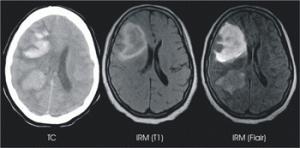

El ictus es una enfermedad cerebrovascular que se produce por la disminución u obstrucción del flujo sanguíneo.